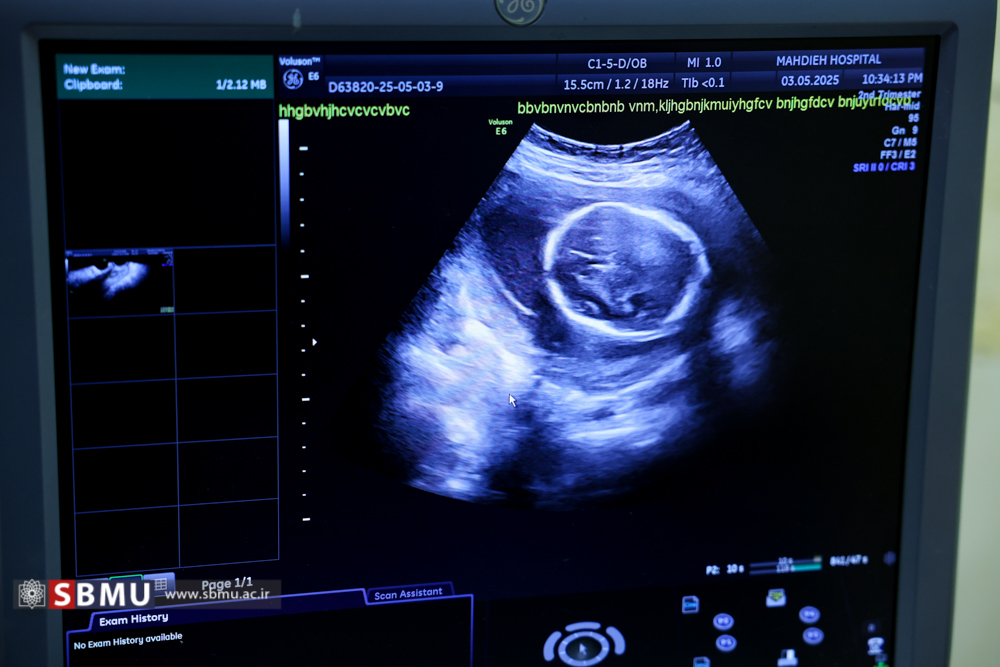

زینب اوسطی، مامای بیمارستان مهدیه شیفت‌های شب در این بیمارستان مشغول به فعالیت است. وی قبل از ساعت 7 عصر به سمت بیمارستان حرکت می‌کند. زینب اوسطی متولد سال 1360، دارای سه فرزند است و برای رسیدگی به فرزندانش، شیفت شب بیمارستان را پوشش می‌دهد. ساعت آغاز شیفت، 7 شب است و تا 7 صبح ادامه دارد. زینب اوسطی چهارمین فرزند خود را باردار است. وی حدود هفت ماهه باردار است. او پس از ورود به بیمارستان برای حضور در بخش آماده می‌شود. شیفت خود را با تحویل شیفت قبلی آغاز می‌کند. و در جریان وضعیت مادران باردار حاضر در بخش قرار می‌گیرد. یکی از مهمترین وظایف ماما، پاسخگویی و راهنمایی همراهان مادران باردار است. مامای بیمارستان مهدیه به مادران در بخش مراقبت ویژه نوزادان، نحوه شیردهی را آموزش می‌دهد. زینب اوسطی مامای بخش مراقبت‌های مادران باردار PLC بیمارستان مهدیه است. زینب اوسطی در هفته بیست و هفتم بارداری، برای اطلاع از وضعیت جنین خود سونوگرافی می‌کند. حجم کاری بالا او را نسبت به مراقبت از فرزند خود حساس‌تر کرده است. زینب اوسطی در حال رسیدگی به امور نوزادان است. مامای بیمارستان مهدیه به مادران در بخش مراقبت ویژه نوزادان، نحوه شیردهی را آموزش می‌دهد. زینب اوسطی در بخش مراقبت‌های ویژه نوزادان حضور دارد. وی در حال بررسی وضعیت مادران در ساعات انتهایی شیفت خود است. شیفت مامای بیمارستان مهدیه 7 صبح به پایان می‌رسد. زینب اوسطی پس از پایان شیفت برای خروج از بیمارستان آماده می‌شود. مامای بیمارستان مهدیه به محض ورود به منزل، نقش مادر سه فرزند را برعهده دارد و همسر وی برای آغاز روز کاری آماده می‌شود. روزها در این خانه با صرف صبحانه آغاز می‌شود. فرزند کوچک او، فاطمه زهرا 3 سال و فرزند وسطی، محمدعلی